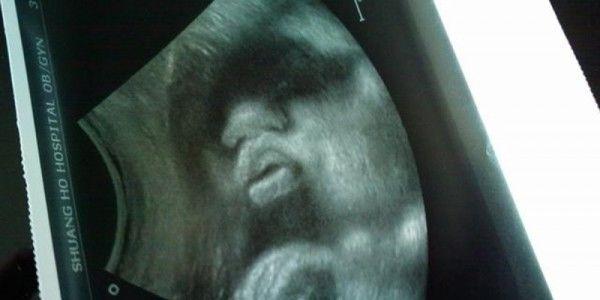

小丽跟老公结婚好几年了 , 好不容易终于怀上了宝宝 。 那时候一家人特别想知道孩子的性别 , 小丽姐姐刚好是妇产科的 , 于是怀孕六个月便找到她姐姐帮忙做孕检 。 姐姐检查后告诉小里孩子是男孩 , 因为图像显示孩子两腿之间有凸起的东西 。

小丽很高兴 , 于是后面孕检就没有再去麻烦姐姐了 , 而是去其他医院检查的 。 那一次检查 , 她随口问了一句:医生 , 我的儿子长的怎样了啊 。 医生笑了笑说:谁告诉你怀的是儿子 , 明明就是个好闺女嘛 , 长得挺好的 , 以后可以少买套房子了 。

明明第一次检查是男宝 , 为什么第二次检查是女宝呢?这下小丽怎么想都想不通 , 医生又不肯告诉实情 , 没办法只要是宝宝健康就可以了 。

于是就一直等到生产的时候 , 当看到孩子的那一刻 , 全家人都懵了 , 原来是一个儿子 。 后来小丽老公问了医生 , 医生才告诉实情 , 原来很多医生为了医德 , 才会故意把孩子的性别说反的 。

居然是这回事 , 小丽总算明白了 , 不管怎样 , 总让人觉得很生气 。